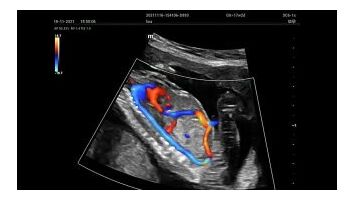

В гинекологии применяются специализированные программы и датчики, позволяющие качественно провести внутриполостные исследования.

В ветеринарии используются портативные или стационарные ультразвуковые системы для животных с использованием, как правило, конвексного/микроконвексного датчика, секторного фазированного и линейного.